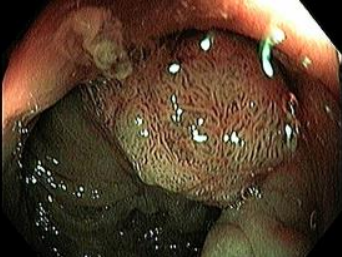

Extirpación de Tumores -

Mucosectomía

Extirpación de Tumores Incipientes

Esófago - Estómago - Cólon